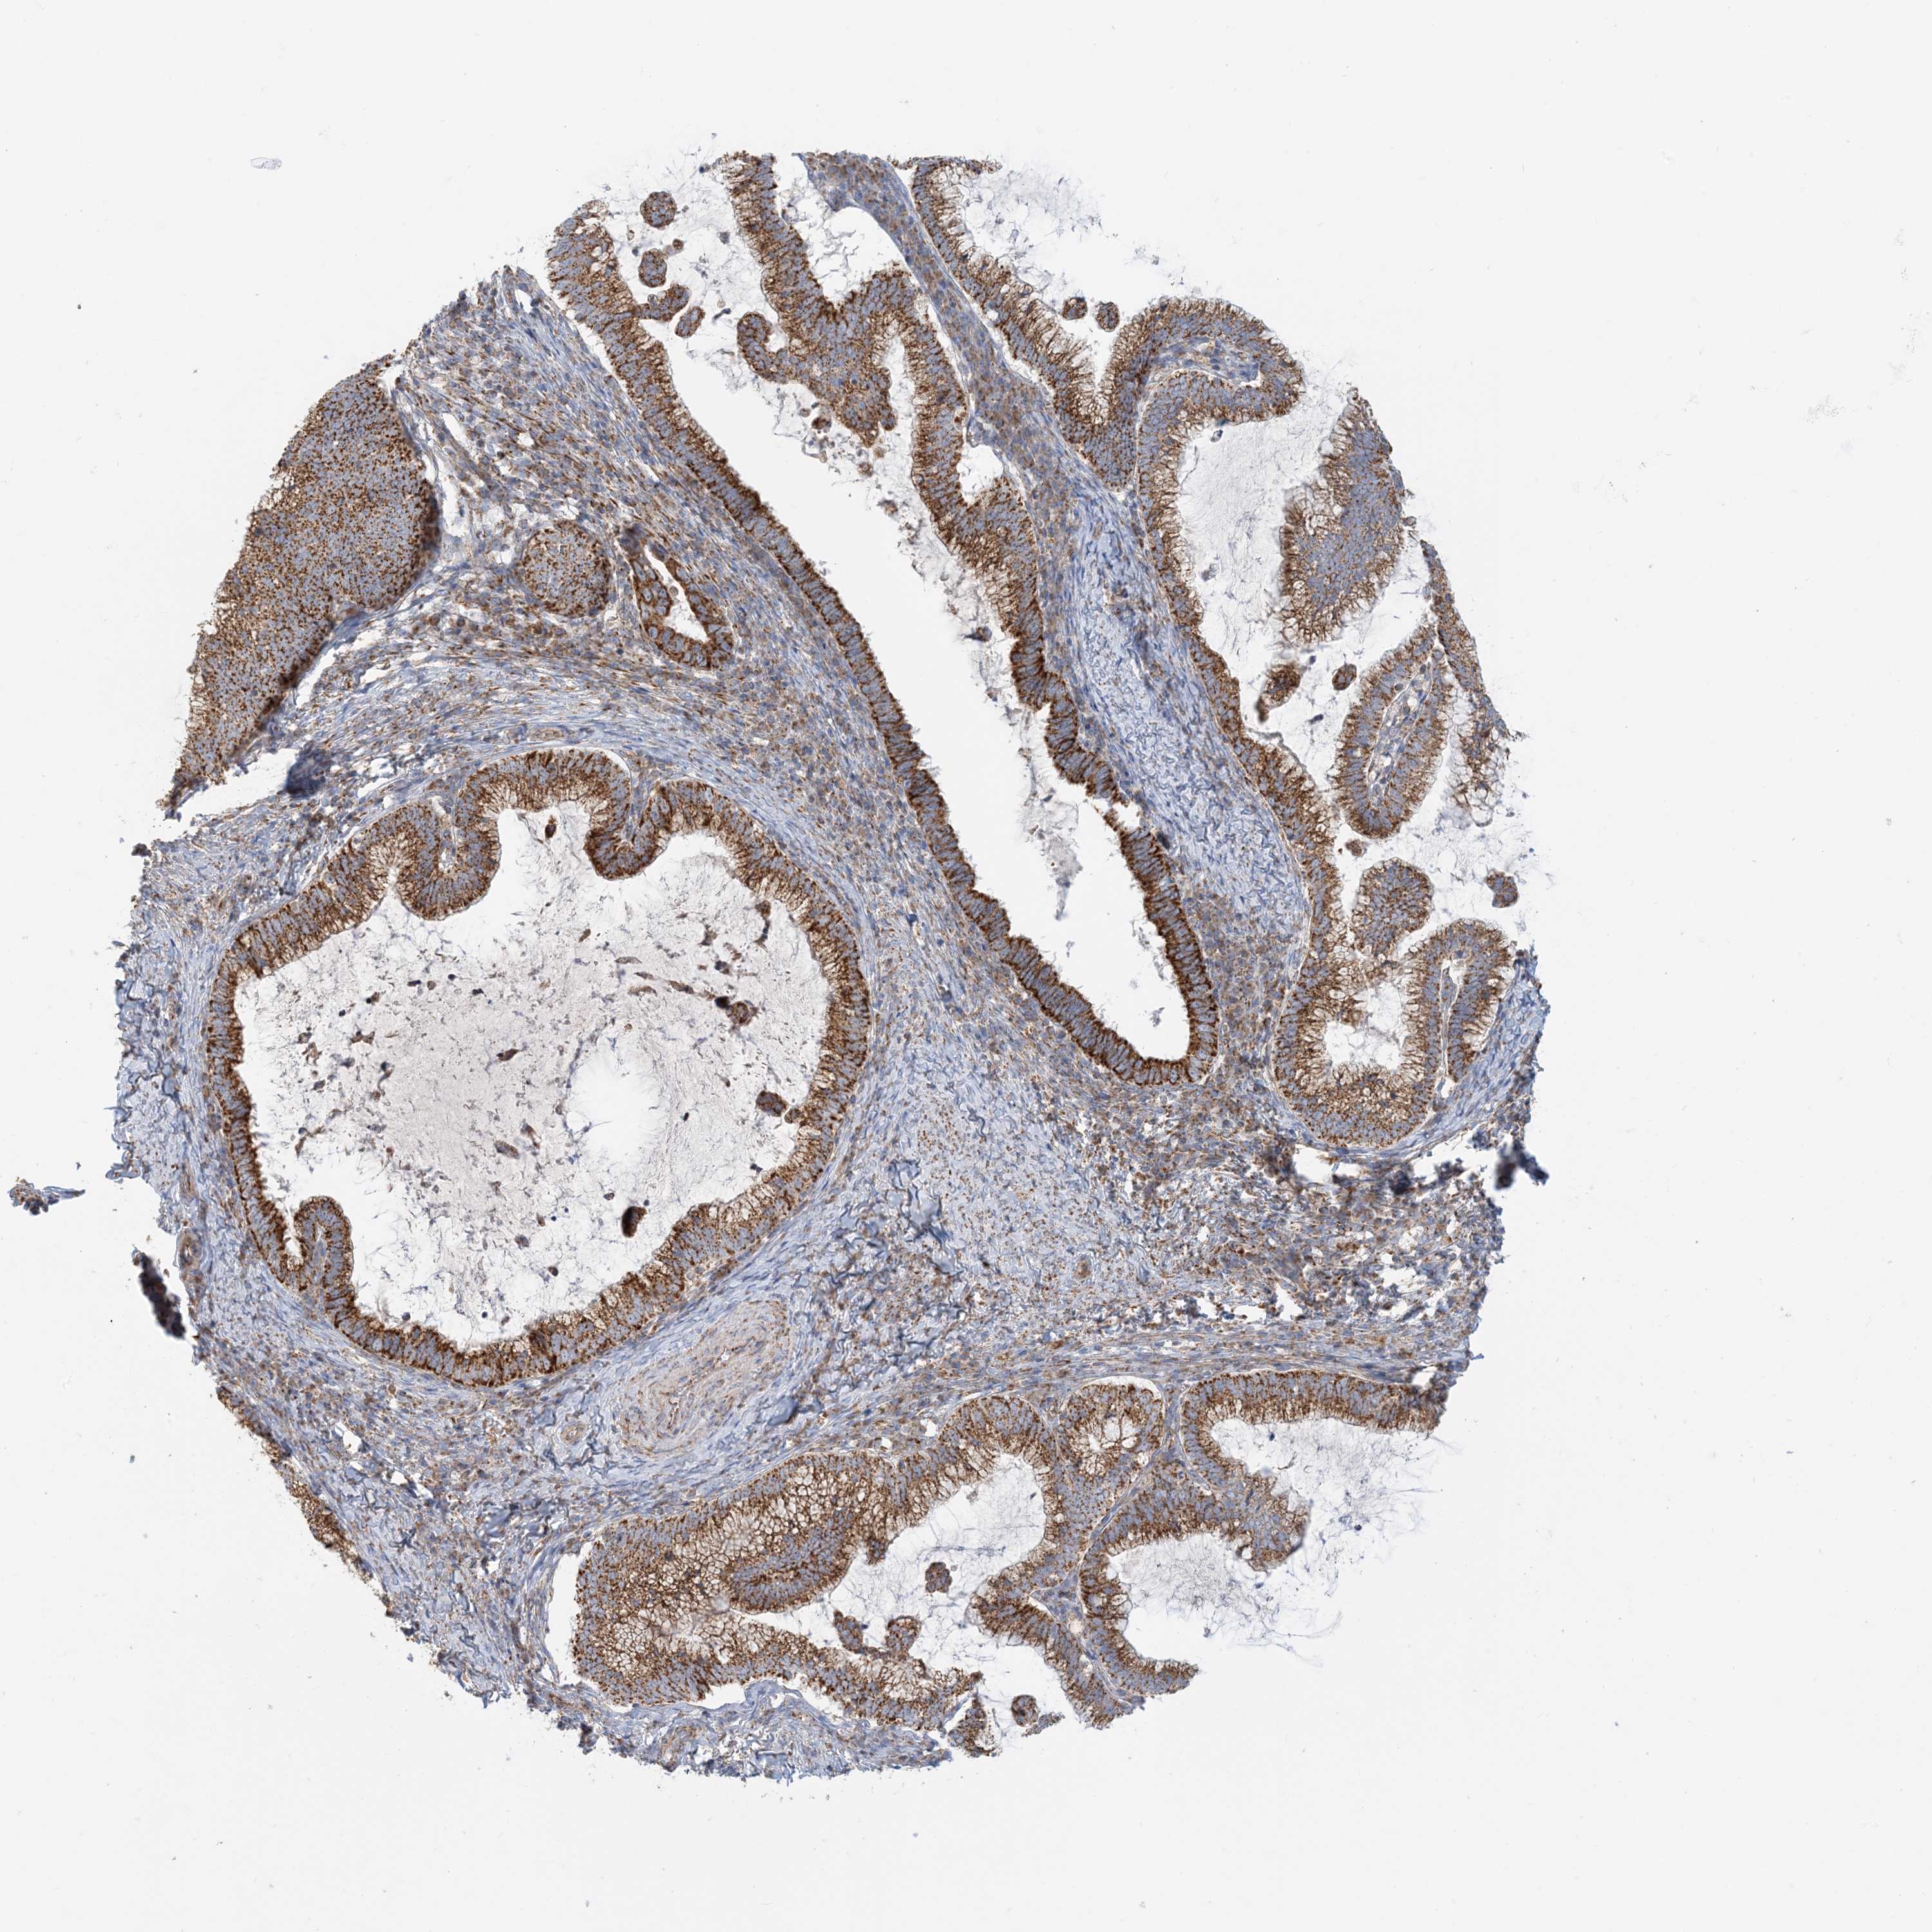

CERVICAL CANCER - Protein expressioni

A mouse-over function shows sample information and annotation data. Click on an image to view it in a full screen mode. Samples can be filtered based on level of antibody staining by selecting one or several of the following categories: high, medium, low and not detected. The assay and annotation is described here.

Note that samples used for immunohistochemistry by the Human Protein Atlas do not correspond to samples in the TCGA dataset.

Antibody stainingi

Antibody staining in the annotated cell types in the current human tissue is reported as not detected, low, medium, or high, based on conventional immunohistochemistry profiling in selected tissues. This score is based on the combination of the staining intensity and fraction of stained cells.

Each image is clickable and will lead to virtual microscopy that enables deeper exploration of all samples and also displays staining intensity scores, fraction scores and subcellular localization as well as patient and tissue information for each sample.

Antibody HPA031966

Staining

High

Medium

Low

Not detected

Intensity

Strong

Moderate

Weak

Negative

Quantity

>75%

75%-25%

<25%

None

Location

Nuclear

Cytoplasmic/membranous

Cytoplasmic/membranous,nuclear

Squamous cell carcinoma, NOS

Adenocarcinoma, NOS